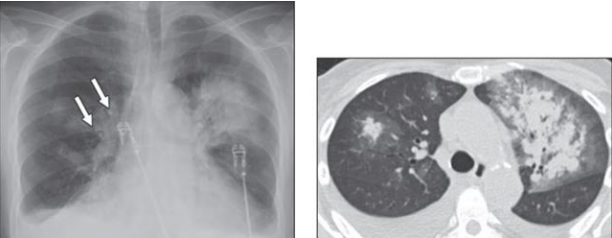

胸部CT

胸部CT可见双肺大片渗出实变影(图1)

图1  患者胸部CT(2020-10-09)